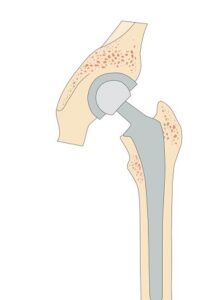

Το ισχίο είναι η άρθρωση που συνδέει τον κορμό μας με τα κάτω άκρα (εικόνα 1 ). Βρίσκεται στο κάτω μέρος της λεκάνης, δεξιά και αριστερά. Στη θέση αυτή υπάρχει μια κοίλη υποδοχή, που ονομάζεται «κοτύλη». Αυτή, υποδέχεται το σφαιρικό άνω τμήμα του μηριαίου οστού, που ονομάζεται «κεφαλή». Τόσο η κοτύλη, όσο και η κεφαλή, καλύπτονται από αρθρικό χόνδρο, ο οποίος εξασφαλίζει την ομαλή κίνηση με ελάχιστες τριβές. Η κοτύλη, κατά κάποιο τρόπο αγκαλιάζει την κεφαλή, σε μια άρθρωση που με όρους κινηματικής περιγράφεται ως «σφαίρα εντός υποδοχής» ή διεθνώς βιβλιογραφικά «ball in socket». Το εντυπωσιακό αυτής της δομής είναι ότι συνδυάζει πολύ μεγάλο εύρος κίνησης με πολύ μεγάλη σταθερότητα.

Στην περίπτωση της οστεοαρθρίτιδας τελικού σταδίου (εικόνα 3 ) πρέπει να γίνει Ολική Αρθροπλαστική του ισχίου. Πρέπει, δηλαδή, η κατεστραμμένη άρθρωση να αντικατασταθεί από μια τεχνητή. Στη θέση της κοτύλης εμφυτεύεται ένα κυπέλιο τιτανίου. Μέσα σε αυτό ενσωματώνεται μια κοίλη υποδοχή από ειδικού τύπου υλικό που αναπαριστά την κοτύλη. Αντίστοιχα, στο μηρό εμφυτεύεται ένας στυλεός, τιτανίου κι αυτός, με κεραμική σφαιρική κεφαλή. Με το «ταίριασμα» αυτών των δύο δημιουργείται το νέο τεχνητό ισχίο (εικόνα 4 , εικόνα 5 και εικόνα 6 ): το εύρος κίνησης αποκαθίσταται και οι τριβές είναι ελάχιστες.